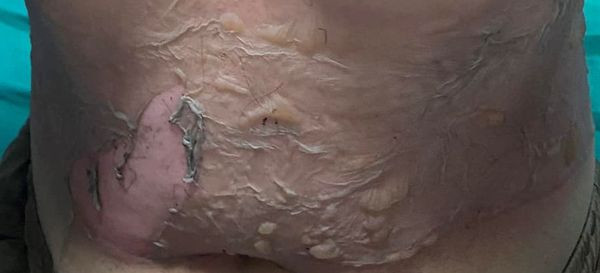

Bệnh nhân nữ 26 tuổi vào bệnh viện Đa khoa Hùng Vương cấp cứu trong tình trạng đau rát vùng mặt, cổ, bụng và cẳng bàn tay 2 bên, diện tích bỏng ước tính khoảng 20%, các tổn thương bỏng độ II, độ III…do bị bỏng lửa cồn và chưa xử trí gì.

| Bệnh nhân bị bỏng cồn nặng |

Các bác sĩ đa khoa Hùng vương cho biết, bỏng cồn rất nguy hiểm. Với những bệnh nhân bị bỏng lửa do cồn, tùy theo mức độ, diện tích bỏng, khi khỏi thường để lại sẹo co rúm trên da, thời gian điều trị khá lâu và khó khăn đối với những trường hợp bỏng nặng. Thậm chí, sẽ để lại sẹo và gây nguy hiểm đến tính mạng.